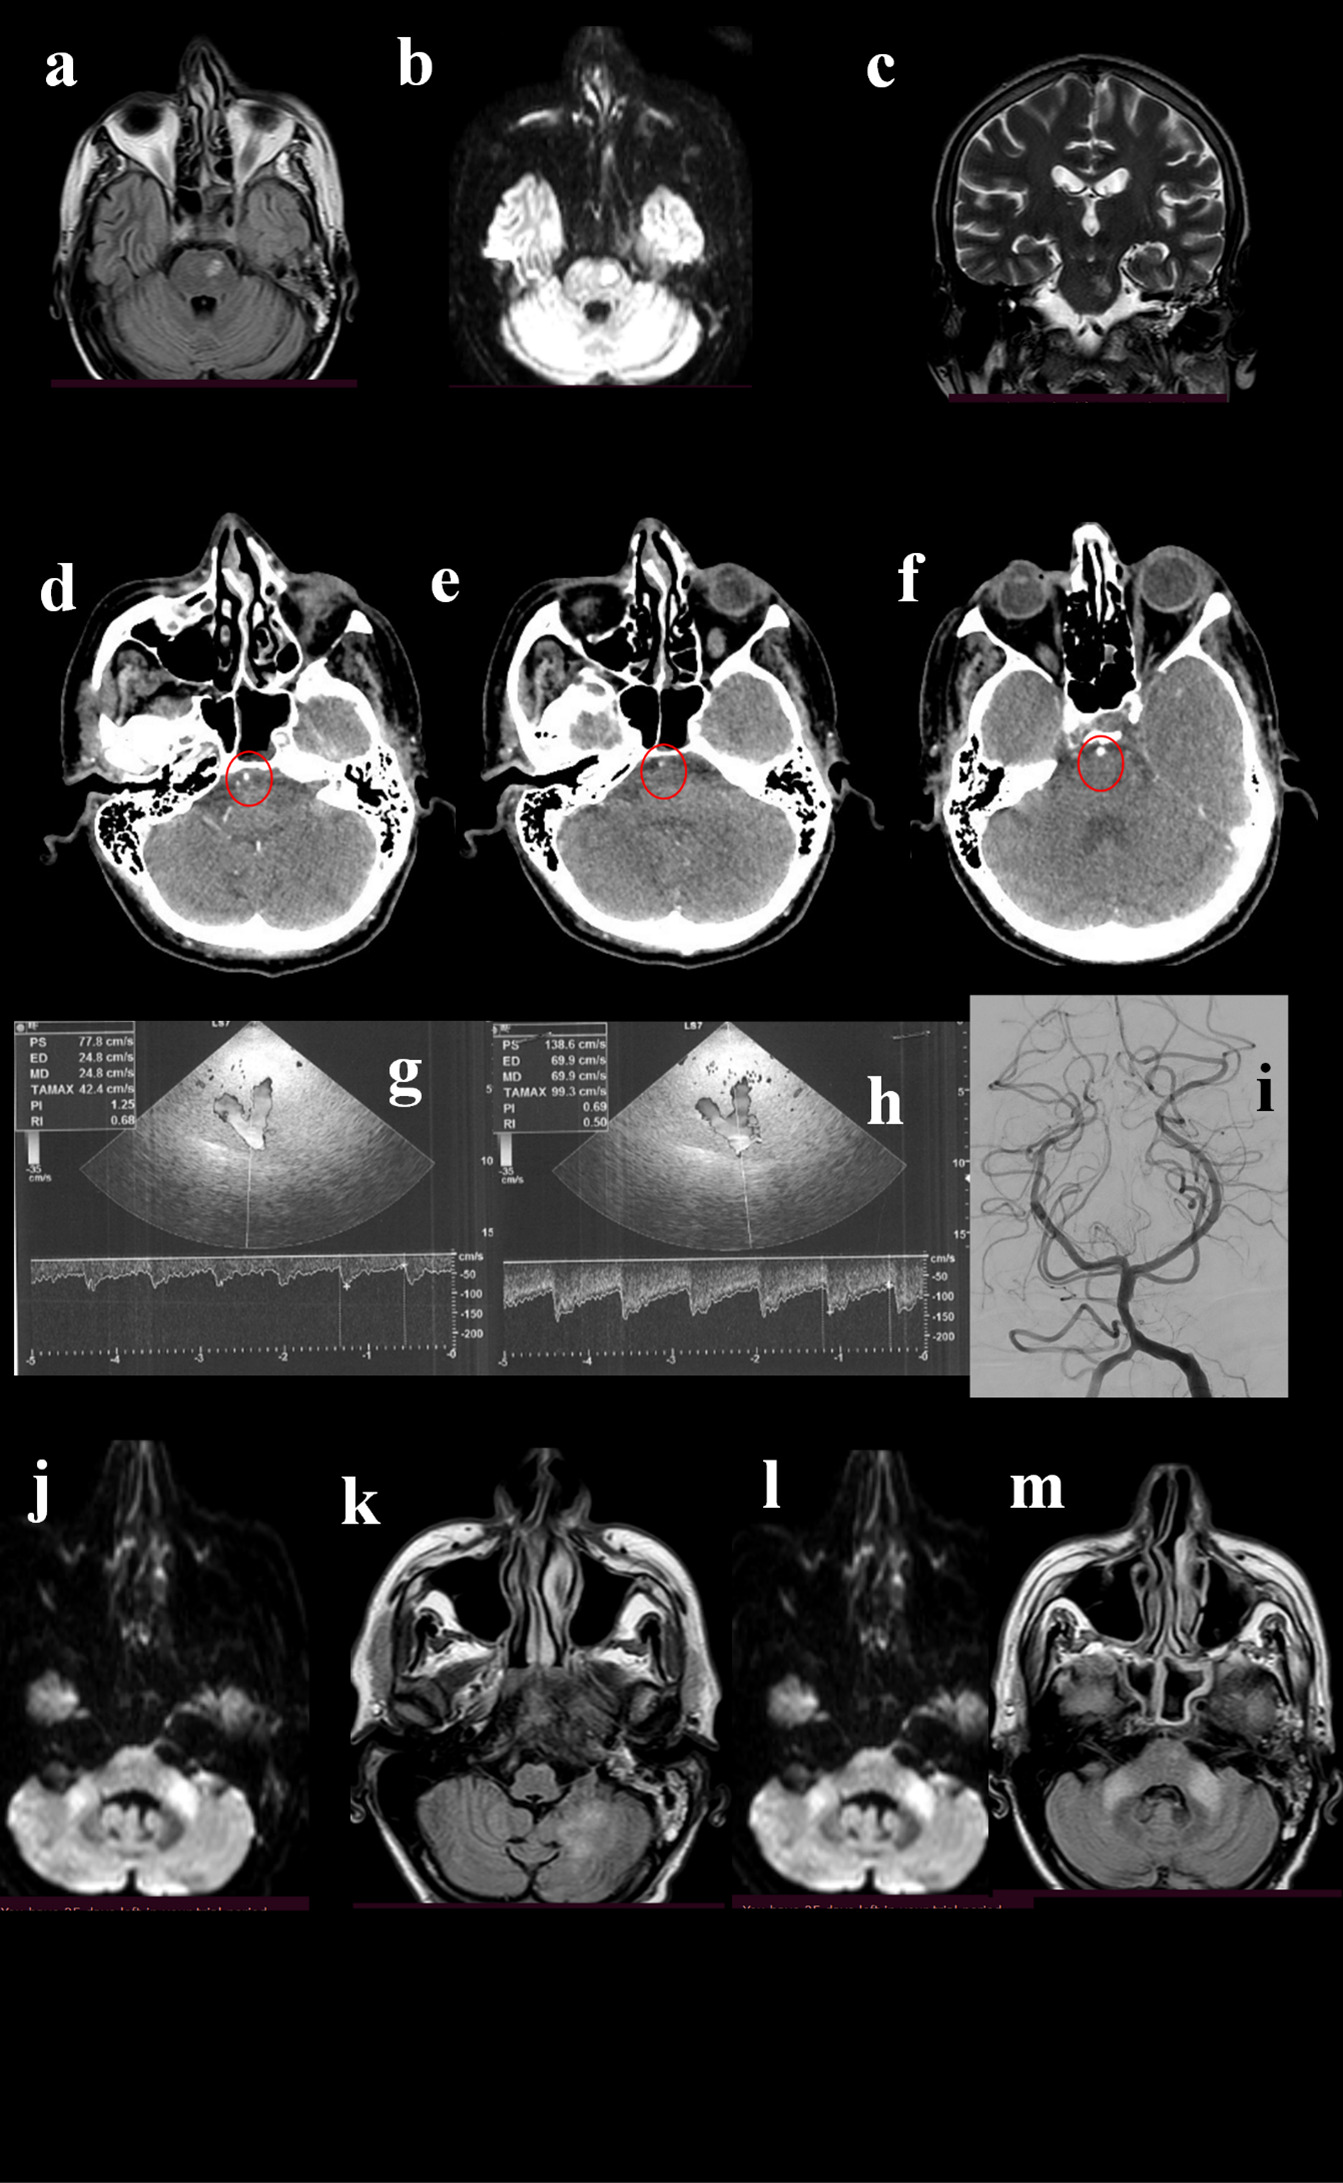

Figure 2. A 49-year-old man was admitted to the hospital for repetitive episodes of acute reduced strength of the right limbs and subsequent fall in last weeks. His past medical history revealed smoking, past episodes of syncope and diplopia started a few months before. The neurological examination showed deficit of left lateral rectus muscle, right VII cranial nerve palsy, mild hyposthenia of right limbs; normal deep tendon reflexes; ataxia. The brain MRI showed FLAIR-(a), DWI-(b), and T2-(c) positive lesion in the left pons. The patient underwent CTA, that showed a normal basilar origin (d, circle) followed by a narrowing (e, circle), and then a normalization of caliber (f, circle). TCCS detected normal flow at the basilar origin (g), while a 1 cm after the origin of the vessel an increase of the flow velocity was observed (h), indicating moderate stenosis (>50%). DSA pointed out the stenosis (i), even if it was not considered suitable for stenting. Thus, the best medical treatment was suggested. One month later the patient was re-admitted for novel clinical worsening, and MRI showed hyperintensities in DWI and FLAIR sequences at bilateral middle cerebellar peduncles (j, k) and at left cerebellum (l, m).